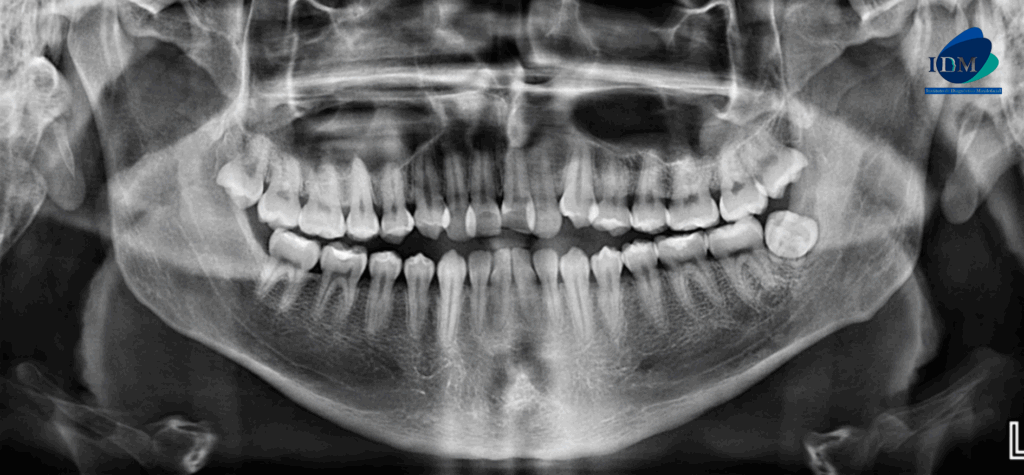

Paciente masculino de 22 años acude al Instituto de Dianóstico Maxilofacial para realizarse una tomografía macizofacial para la colocación de ortodoncia. A la evaluación de la radiografía panorámica se observa la neumatización de ambos senos maxilares, apiñamiento dental anterior, múltiples restauraciones coronarias y la pieza 48 distoangulada y torsión bucolingual.

Radiografia Panorámica